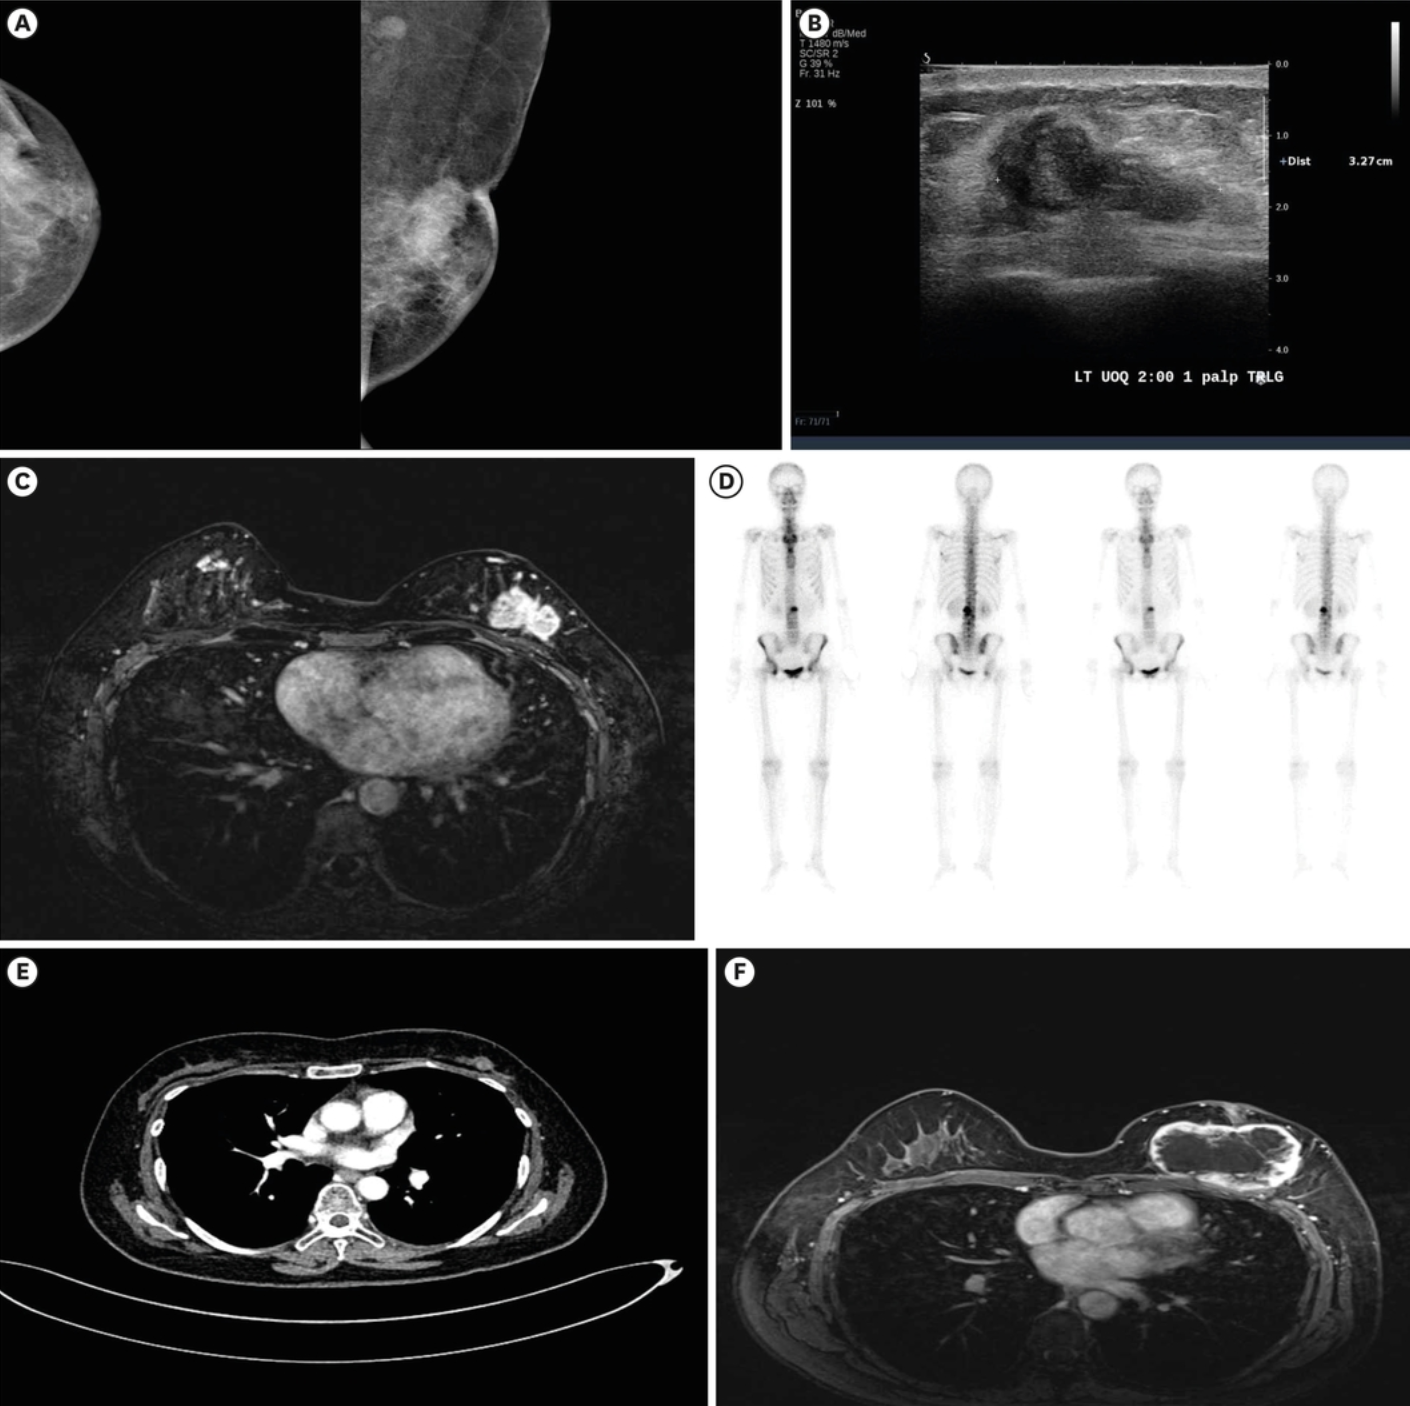

体格检查发现左侧UOQ有一不规则、质硬肿块,大小约3.0 × 2.5 cm,伴有皮肤和乳头回缩。初次乳腺X线片显示左侧UOQ有一4.4 cm的高密度肿块,伴有皮肤回缩,提示皮肤侵犯,左侧腋窝有一1.3 cm的增大淋巴结(图1A)。乳腺超声和磁共振成像(MRI)显示,左侧UOQ有一3.5 × 1.3 × 3.3 cm的不规则低回声主肿块,伴有乳头和皮肤侵犯,左乳房有多中心病灶,左侧腋窝I级有两个可疑淋巴结(图1B和C)。

图1 乳腺和转移性病变的影像学表现(A)初始乳腺X线片:左侧UOQ有一4.4 × 2.1 cm的高密度肿块,伴有皮肤回缩,提示皮肤侵犯,左侧腋窝有一增大的淋巴结。(B)初始乳腺超声:左侧UOQ的3.5 × 1.3 × 3.3 cm不规则低回声肿块经证实为恶性肿瘤。(C)初始T1动态减影增强MRI:证实左乳外侧半部有恶性肿瘤(3.4 × 2.4 × 4.1 cm),伴有皮肤和乳头回缩。(D)初始骨扫描:T5、L2和双侧坐骨有多发骨转移病灶。(E)接受24个周期瑞波西利和芳香化酶抑制剂治疗72周后胸部计算机断层扫描(左乳房肿块1.3 cm)。(F)接受30个周期治疗90周后MRI:左乳房可见一个7.6 × 5.0 cm的环形增强肿块,形态和边缘不规则。UOQ = 乳房外上象限;MRI = 磁共振成像。

乳房肿块的核心穿刺活检结果为非特殊类型浸润性乳腺癌。根据Allred评分系统,患者被诊断为雌激素受体:8,孕激素受体:8,C-erbB2:阴性的Luminal A型乳腺癌。患者无血行性肺部或腹部转移,但经骨扫描和腰椎经皮骨活检证实存在T2和T5脊柱转移性癌(图1D)。根据《美国癌症联合委员会第八版癌症分期》,临床分期为T2N1M1;因此,患者接受了瑞波西利+AI+戈舍瑞林醋酸酯联合地诺单抗的一线姑息性化疗。

在开始一线姑息性化疗前,全血细胞计数显示白细胞增多和血小板增多(白细胞:16,240/μL,血红蛋白:16.4 g/dL,血小板:970,000/μL);因此,进行了骨髓检查,证实为JAK2 V617F突变阳性(49.3%)的骨髓增殖性肿瘤。治疗方案中增加了阿司匹林(100 mg/天)。在接受72周(24个化疗周期)的胸部计算机断层扫描后,左乳房的主病灶显著缩小至1.3 cm(图1E),骨转移病灶也保持稳定。患者继续接受瑞波西利 +AI+戈舍瑞林醋酸酯姑息治疗18周(额外6个化疗周期)。

在完成90周(30个周期)瑞波西利+AI+戈舍瑞林醋酸酯姑息治疗后的评估中,肿瘤标志物和骨转移病灶持续显示病情稳定;然而,一个形状和边缘不规则的环形增强肿块突然增大,占据了整个左乳房(7.6 × 5.0 cm),并伴有肌肉和皮肤侵犯(图1F)。鉴于病灶的快速增大、临床症状以及影像学表现高度提示局部复发,因此在未进行核心穿刺活检的情况下,进行了改良根治性乳房切除术。术后活检显示,左乳房肿块大小为8.5 × 8.0 cm,大体标本呈结节状,局部浸润至周围脂肪组织;但在乳头或皮肤中未观察到癌症成分(图2A)。